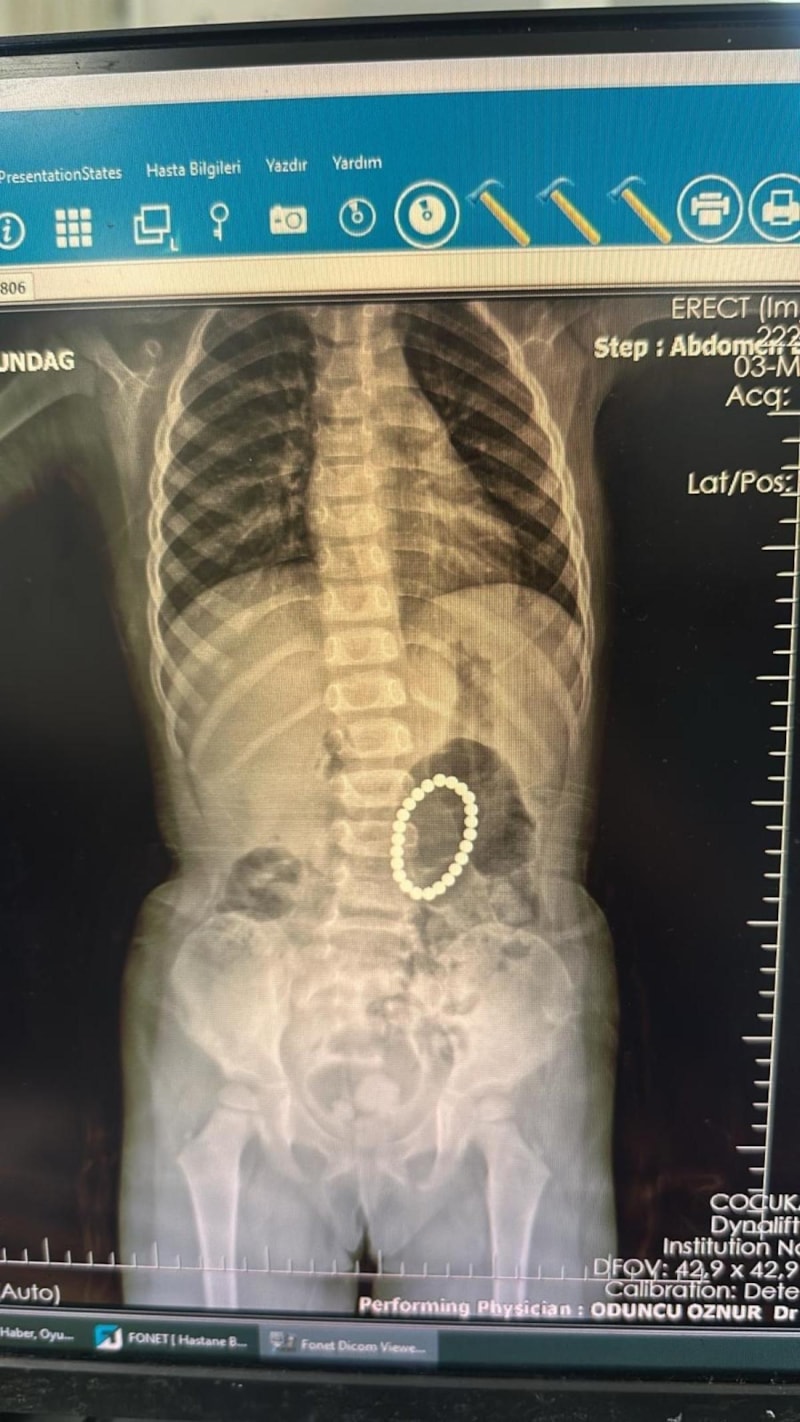

Yapılan endoskopide küçük kızın bağırsaklarında ve midesinde bileklik şeklinde yabancı cisimlerin olduğu belirlendi.

Ameliyata alınan Rumeysa Altundağ'ın bağırsakları ve midesinden 24 adet renkli oyuncak mıknatıs çıkartıldı.

Bunun üzerine endoskopi yapılmak üzere hastanemize Gastroentoloji bölümüne sevk edildi. Endoskopi sırasında tespit edilen yabancı cisimlerin renkli mıknatıslar olduğu, yarısının da midede gözükmediği görüldü. Hastamız 24 tane renkli küçük mıknatıs yutmuştu.

Endoskopi işleminden sonra hastamıza operasyon planladık. Yaptığımız ameliyatta da farklı zamanda yutulan mıknatısların yarısının midede yarısının bağırsaklarda olduğu ve bunların birbirine yapışarak bağırsak kısımlarında delinmelere neden olduğu görüldü.